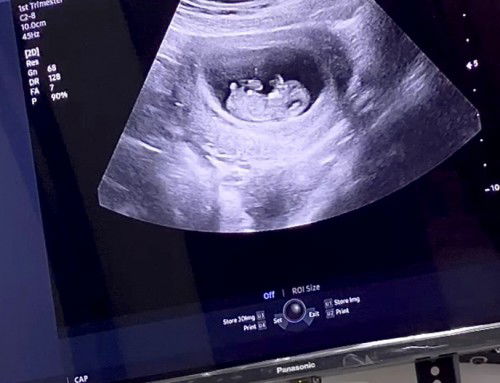

Hi mama2 online ku … nama saya baby S . Saya dah 10weeks++ … lagi 1 week+ saya dah masuk trimester 2 . Harap semua mama online sihat and kuat ye jaga and lahirkan kawan2 saya 💪🏻 saya asyik buat mama lapar , dahaga . 😥 kadang saya tak bagi mama tido . kalau saya penat saya nak mama tido lama2 . 😮💨 14hb ni saya NT scan . doakan saya sihat ye mama2 online ku 💋 mama2 online saya dah berapa weeks ? 💕 #firstbaby #firstmom #10weeks5days #firsttrimester #babyjan2023